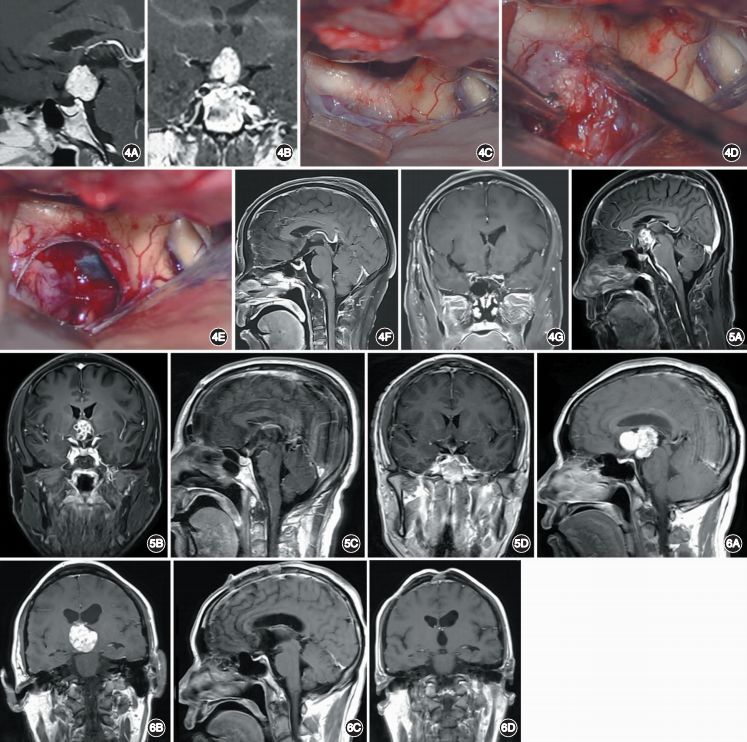

4. 第三脑室型:肿瘤主体完全位于第三脑室内部。因为考虑到肿瘤位置和鞍底以及前颅底结构之间有第三脑室底部及视神经等结构相隔,神经内镜经鼻入路会破坏第三脑室底部结构,所以不建议采用神经内镜经鼻入路手术[12]。一般选择开颅手术,手术入路有两种:经终板入路和经胼胝体-穹窿间入路。当肿瘤主体位于第三脑室前下部时,适合选择经终板入路(图5);位于第三脑室后上部并贴近穹窿时,则适合选择经胼胝体-穹窿间入路(图6)。但是,Forbes等[13]认为部分第三脑室内型颅咽管瘤同样可以使用神经内镜经鼻入路手术并可获得良好的疗效。对于第三脑室内型颅咽管瘤,从手术安全角度出发,建议采用幕上开颅手术。

图4. 位于鞍背后方的鞍上型颅咽管瘤患者的影像学资料和术中所见。A,B.术前矢状位(A)和冠状位(B)增强MRI显示肿瘤位于鞍背后方;C~E.术中可见视交叉前方及视神经、颈内动脉间隙均无法看到肿瘤(C),之后切开终板充分显露肿瘤(D)并将其完全切除(E);F,G.术后矢状位(F)和冠状位(G)增强 MRI显示肿瘤完全切除。图5. 选择经终板入路手术的第三脑室型颅咽管瘤患者的影像学资料。A,B.术前矢状位(A)和冠状位(B)增强 MRI显示肿瘤位于第三脑室内,靠近前下方;C,D.术后矢状位(C)和冠状位(D)增强 MRI显示肿瘤完全切除。图6. 选择经胼胝体-穹窿间入路手术的第三脑室型颅咽管瘤患者的影像学资料。A,B.术前矢状位(A)和冠状位(B)增强 MRI显示肿瘤位于第三脑室内,靠近后上方;C,D.术后矢状位(C)和冠状位(D)MRI显示肿瘤完全切除。